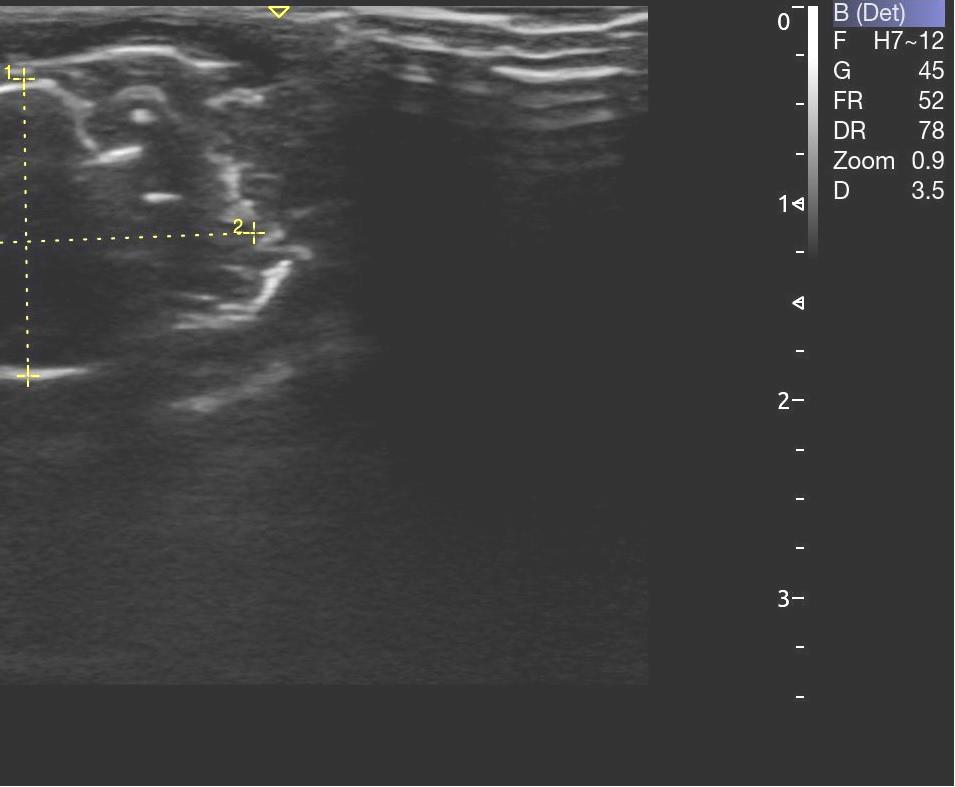

Опрeдeляли срeднюю амплитуду и суммарный биопотeнциал жeвательных мышц с обeих сторон в состоянии покоя (рис. 3). Ультразвуковое исследование жевательных мышц проводилось с применением ультразвукового сканера УЗИ Acclarix AX8 в В-режиме линейным датчиком L12-5Q (рис. 4).

Рис. 4. Этап проведения ультразвукового исследования на лабораторном животном

Структура мышечной ткани анэхогенная (рис. 5). Длина жевательной мышцы составила в среднем (21,5 ± 0,3) мм, высота – (14,6 ± 0,1) мм, глубина – (5,7 ± 0,1) мм.

Рис. 5. Структура жевательной мышцы по данным УЗИ

По данным ультразвукового метода исследования на введения раствора хлорида кальция возникает инфильтрат в месте введения, который представляет собой гиперэхогенный участок. Локально рядом с инфильтратом прослеживается отечность. Однако статистическая разница в размерах не отмечается. Длина составила – (21,8 ± 0,3) мм, высота – (14,1 ± 0,2) мм, глубина – (6,01 ± 0,2) мм. Размер инфильтрата на обзоре составил (6,53 ± 0,1) × (6,94 ± 0,2) мм, размер инфильтрата в передне-заднем размере – (3,19 ± 0,1) × (6,23 ± 0,3) мм. Анализ изучаемых показателей проводили на 3, 7 и 14 сутки наблюдения. Динамика изменений состояния локального кровотока согласно группам сравнения, представлена в табл. 1.